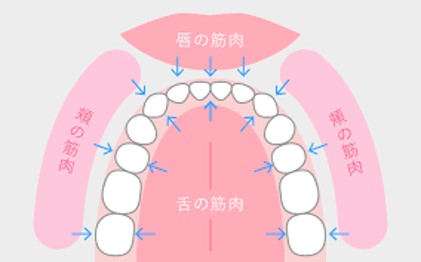

このように、上顎歯列に関しましては唇と頬の筋肉の力が歯列に非常に強く加わっているため、すぼめられたようになってしまったと考えられます。

そこで診断では歯列形状を保つために必要な内外にかかる唇、頬、舌の筋肉のバランスを整えるべくMFTを併用したマウスピースタイプのトレーナーでの治療からスタートすることにしました。